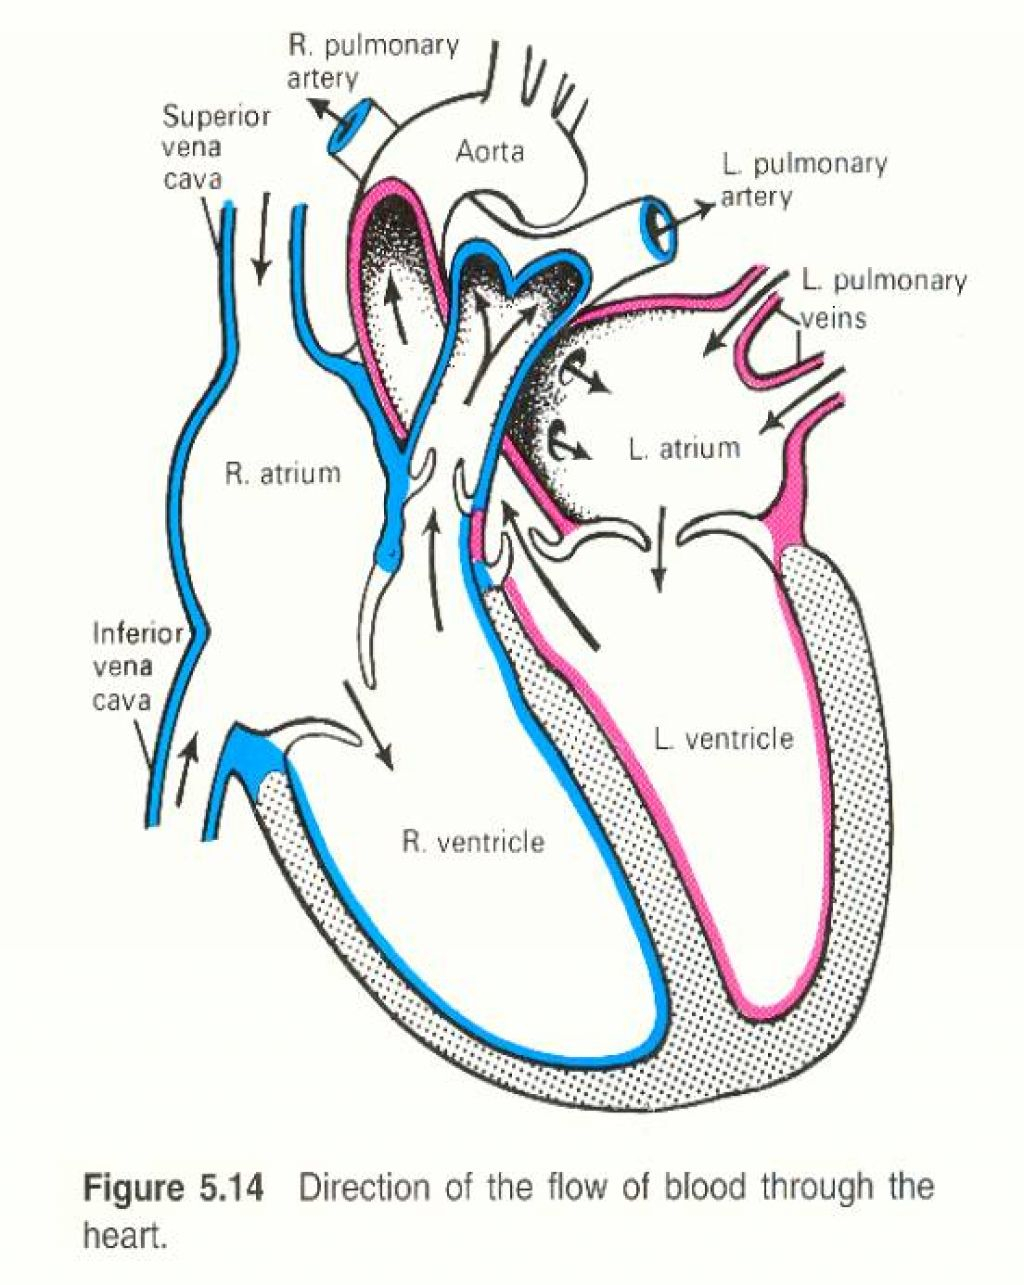

Human heart by kortney16 on DeviantArt  Human Heart-Gross structure and Anatomy - Online Biology Notes

Human Heart Diagrams | 101 Diagrams  Human Heart Simple Drawing at GetDrawings | Free download

Anatomy of the Heart: Physiology | Health Life Media  Human Heart Anatomy Drawing at GetDrawings | Free download

Human Heart - Circulatory System | OER Commons  de Location Of Human Heart In Body mar webmds heart anatomy page provides a detailed image of

Anatomy of the human heart  Human Heart Drawing Line Work stock vector art 481404348 | iStock